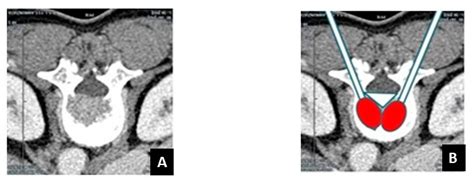

The Role of a Navigational Radiofrequency Ablation Device and ...

mdpi.com